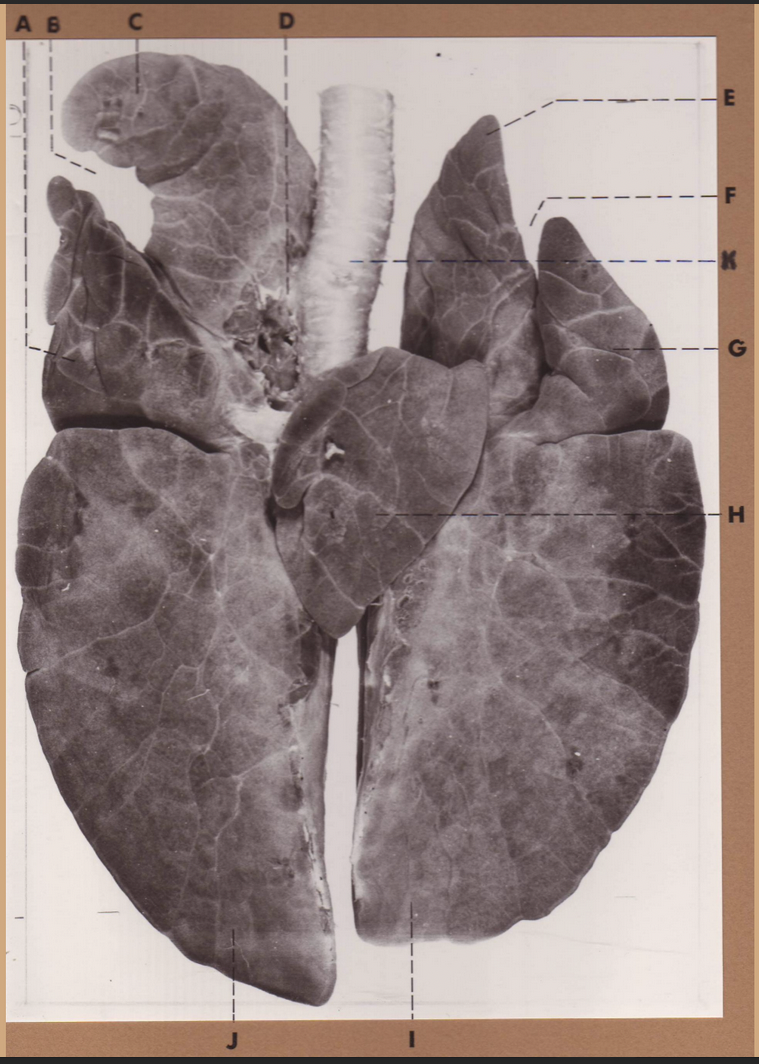

A

(cat larynx/trachea/lungs, dorsal)

epiglottis

B

(cat larynx/trachea/lungs, dorsal)

larynx

C

(cat larynx/trachea/lungs, dorsal)

trachea

D

(cat larynx/trachea/lungs, dorsal)

R cranial lobe

E

(cat larynx/trachea/lungs, dorsal)

middle lobe

F

(cat larynx/trachea/lungs, dorsal)

R caudal lobe

G

(cat larynx/trachea/lungs, dorsal)

primary bronchi

H

(cat larynx/trachea/lungs, dorsal)

L caudal lobe

I

(cat larynx/trachea/lungs, dorsal)

L cranial lobe

J

(cat larynx/trachea/lungs, dorsal)

cricoarytenoideus dorsalis m

K

(cat larynx/trachea/lungs, dorsal)

thyroid